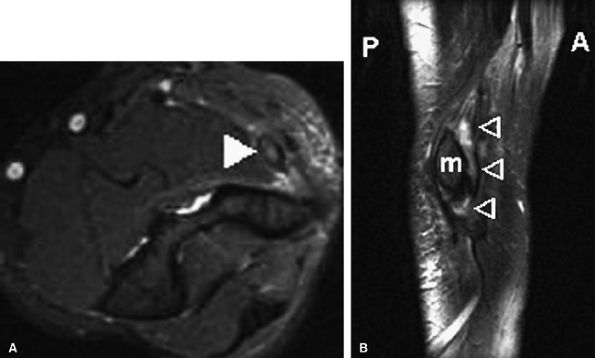

On MR examinations obtained after anterior ulnar nerve transposition, T2 hyperintensity equalize within the ulnar nerve may persist long after the surgery (Fig. 12.27). Intense increased signal, however, is more likely to reflect persistent neuritis. Ulnar nerve thickening can be seen in the first postoperative year in up to 50% of patients following transposition.65 Tethering of the nerve and engulfing scar can also be identified. Other causes

P.1957

for persistent pain after anterior ulnar nerve transposition include extensive scarring or retearing at the resection site of the pronator–flexor muscle group.

FIGURE 12.27 ● Failed anterior ulnar nerve transposition. Axial post-contrast fat-suppressed T1-weighted image (A) and oblique sagittal fat-suppressed T2-weighted image (B) demonstrate increased signal and thickening of the transferred ulnar nerve (arrowheads). m, medial epicondyle.

|